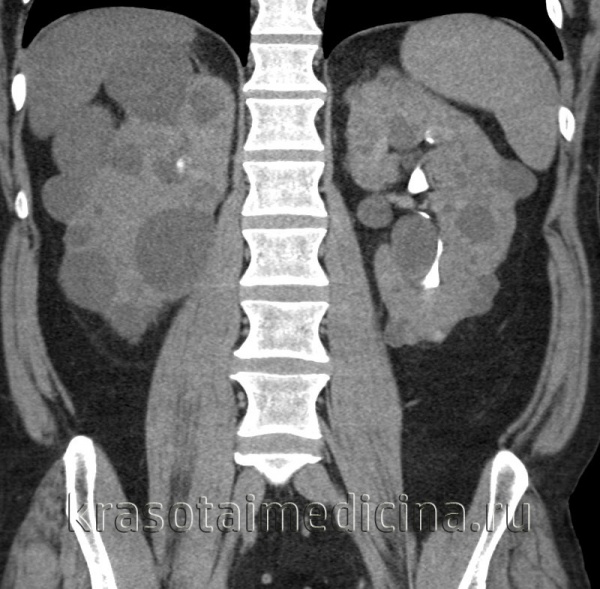

Рисунок 5 | Корональный Т2-снимок пациента с ПКП-АД.

Нарушение нормальной архитектоники обеих почек. Почки увеличенные в размере (более 15 см), нормальная ткань почти полностью замещена кистами различных размеров от нескольких миллиметров до 3 и более см. Большинство кист неосложненные, но некоторые имеют гипоинтенсивные отложения внутри. Кисты в селезенке, печени и поджелудочной железе не обнаружены.